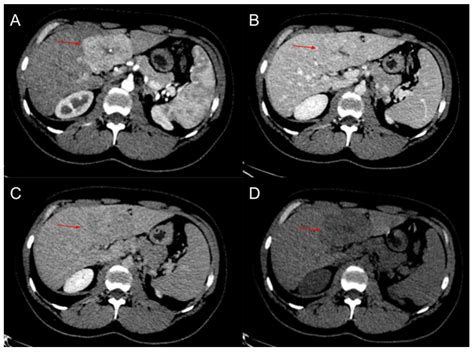

• Computed Tomography (CT) Scan: A CT scan uses X-rays to create detailed images of the liver. It can help differentiate FNH from other liver lesions.

• Magnetic Resonance Imaging (MRI): MRI uses magnetic fields and radio waves to produce detailed images of the liver. It is often the preferred method for diagnosing FNH due to its high sensitivity and specificity.